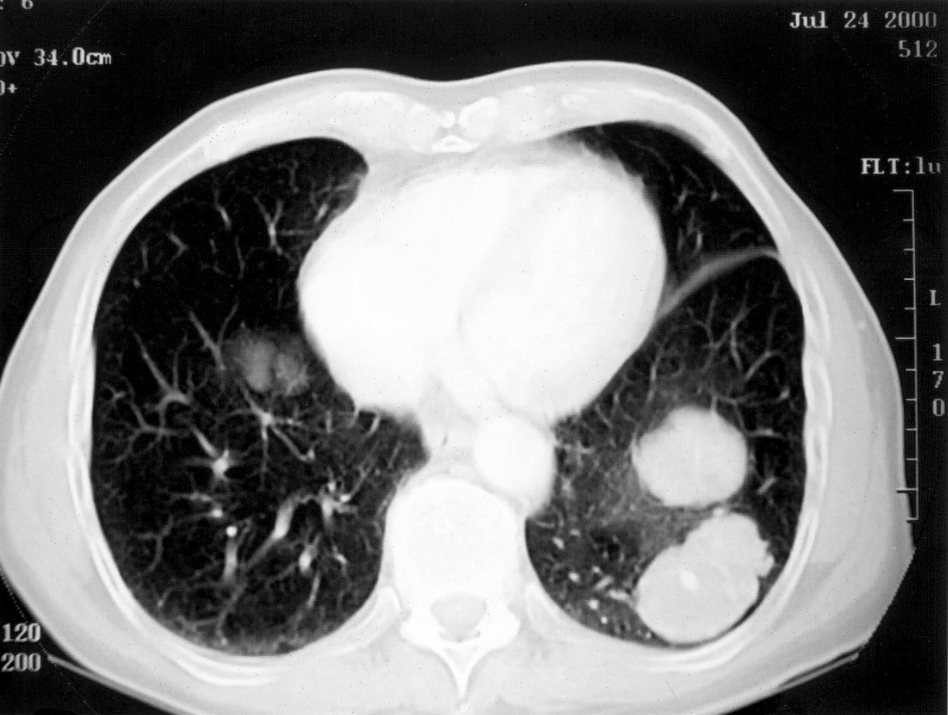

A 78-year old man with an advanced form of lung cancer (malignant fibrous histiocytoma) declined conventional cancer therapy and elected to adhere a daily regimen of 15 grams of omega-3 fish oils (8160 mg EPA, 6840 mg DHA) and over a 4-year period experienced a remarkably slow and steady decrease in the size and number of lung tumors. (see accompanying photos). [Nutrition & Cancer 2005]

Photo credits: Taylor & Francis, Nutrition & Cancer, Volume 52, 2005

(CT) scan performed on July 24, 2000 reveals two large masses in the lower left lobes of the lung.

CT scan performed on April 2, 2004. Tumor masses in lower left lobe are greatly diminished in size.